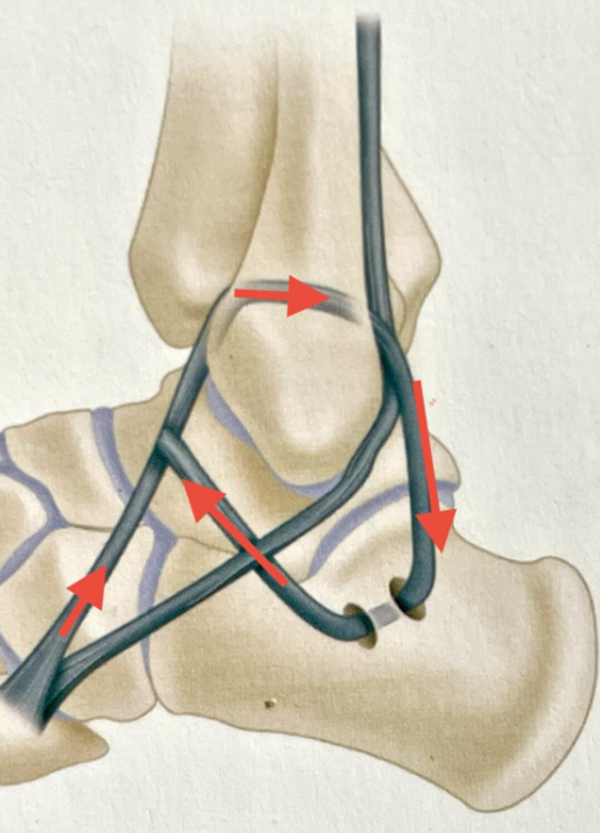

图4 踝关节外侧距腓前、后韧带以及跟腓韧带损伤

3、Chrisman-Snook术式(改良Elmslie手术)

1/2腓骨短肌腱重建距腓前韧带和跟腓韧带,同时加强踝关节和距下的稳定性。

(5)Chrisman-Snook术式(改良Elmslie手术)示意图

图13 肌腱移植方向